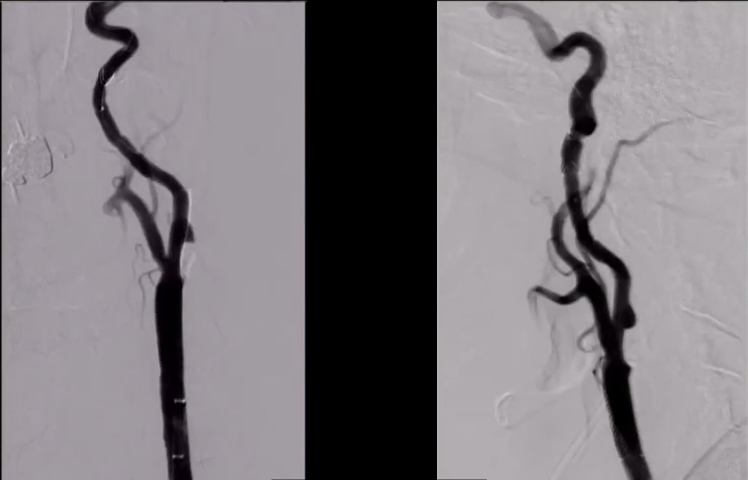

DSA:双侧颈内动脉起始部重度狭窄;前交通及双侧后交通未开放。

8F Fluxcap®球囊导引导管在5FMPA多功能125cm导管同轴辅助下送至右侧颈总动脉,微导丝送至C4段,沿微导丝送入6mm保护伞至C2段平直段,手推造影显示保护伞打开良好。

沿保护伞导丝送入4.0mm×30mm球囊,充盈球囊导引导管的球囊阻断血流,于狭窄段定位后命名压扩张球囊,泄球囊时在球囊导引导管的体外端予以负压回抽血液,取出一2mm血栓。经Fluxcap®球囊导引导管输送7.0-10.0mm×40mm自膨支架(Protégé RX)至狭窄段确认位置后释放。应用125cm多功能导管回收保护伞,多功能导管体外端予以负压回抽血液,保护伞内有血栓。

造影可见残余狭窄10%左右,颅内各分支血管通畅。